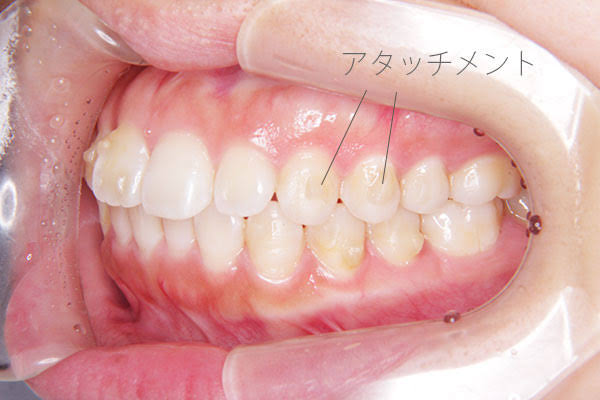

アタッチメントについて【インビザライン矯正の処置】

こんにちは北戸田coco歯科です!透明で薄いマウスピースを装着することで知られているインビザライン矯正。しかし、…[read more]